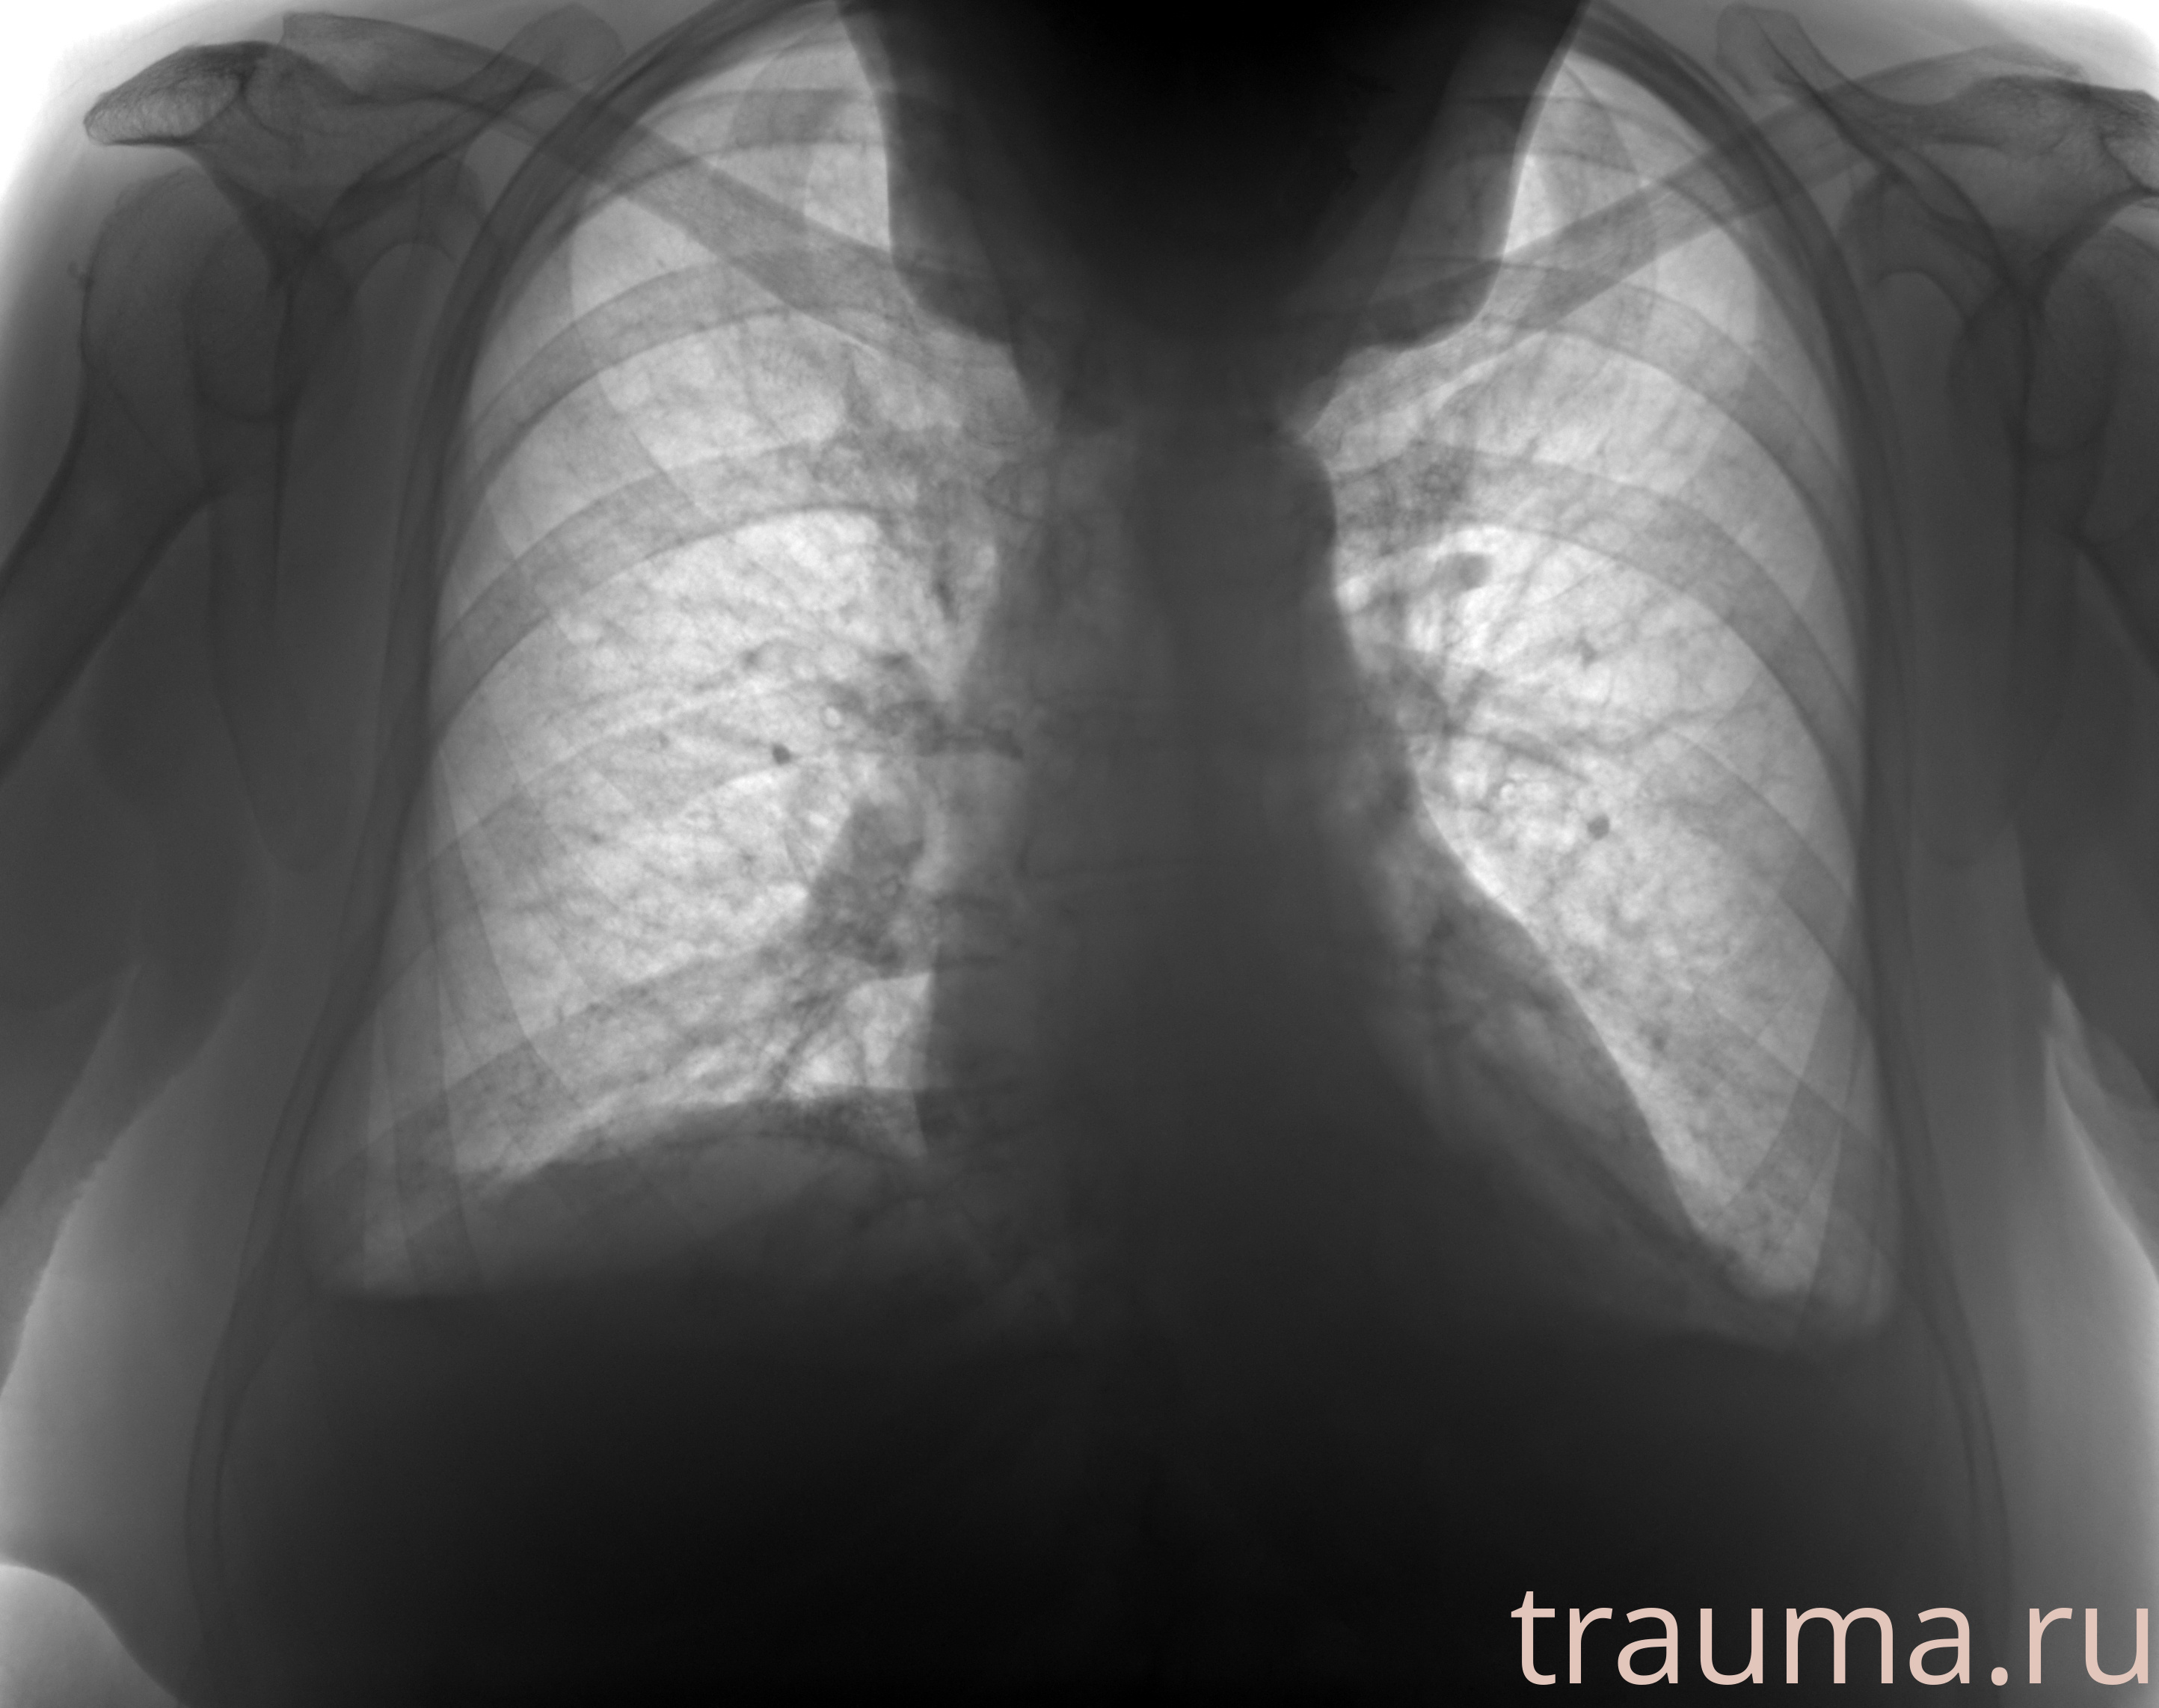

Рентгенограммы

Рентген на дому: по вашему адресу приезжает врач-рентгенолог, травматолог-ортопед с мобильным рентгеновским аппаратом, проводит диагностику травмы или заболевания, делает необходимые рентгенограммы, дает рекомендации по дальнейшему лечению. Получить качественные снимки в домашних условиях возможно благодаря уникальной методике, разработанной МосРентген Центром для института  Склифосовского